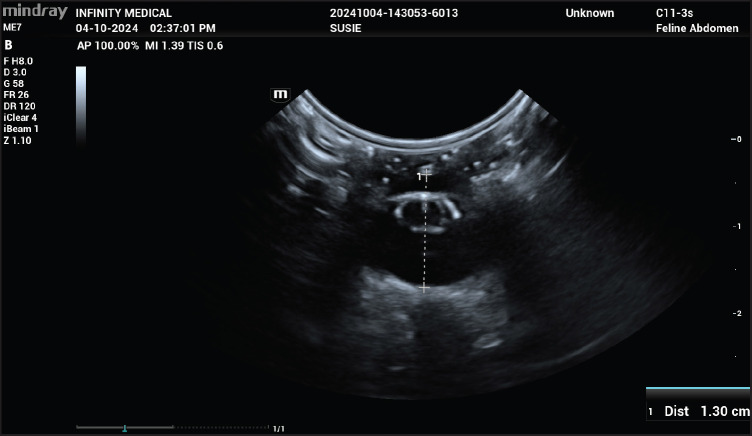

Methods: Five Bornean sun bears diagnosed with cataracts at the Bornean Sun Bear Conservation Centre in Malaysia underwent ocular examination under general anesthesia. Keratometry and biometry data, including anterior chamber depth, crystalline lens thickness, and axial globe length, were collected using an automated keratometer and B-mode ultrasound. The Retzlaff, Binkhorst, Colenbrander, and Fyodorov formulas were used to estimate the required IOL power.

Results: The mean corneal keratometric power was 56.94 D, the mean axial globe length was 12.93 mm, and the mean calculated postoperative anterior chamber depth was 4.77 mm. The mean calculated IOL power was +92.96 D. Conclusion: Aphakic cataract surgery were decided following these findings showing no available commercial IOL implants for this species. These findings provide valuable baseline data for optimizing cataract surgery in Bornean sun bears.